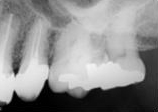

antes depois